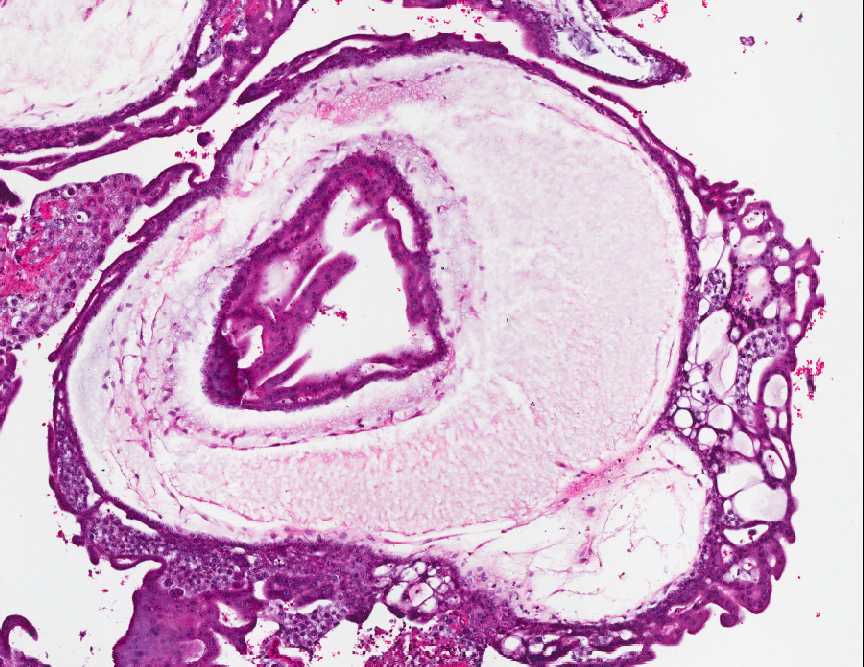

Man erkennt unregelmäßig verzweigte, und deutlich vergrößerte, vielfach ödematös aufgetriebene Zotten. Der Trophoblast mit zirkulärer, medusaartiger Hyperplasie des Synzytiotrophoblasten und intermediären Trophoblasten. Miterfasst dezidualisiertes Endometrium.

Abb. 315: Chorionzotten, molige Degeneration und atypischer Syncytiotrophoblast mit Invagination